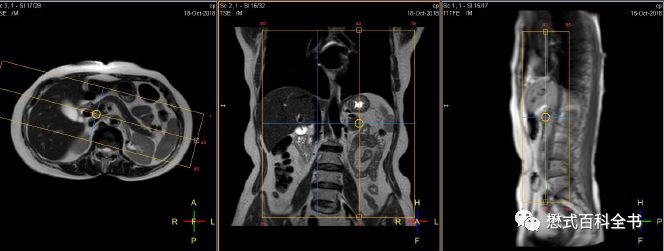

图27:胰头区囊性占位,肝内胆管、胰管扩张(Ingenia 1.5T图像)

有的时候,如果要诊断胆囊结石或者胆管结石,相对难度不大。明显的结石,经常在常规的横轴位T2WI或者冠状位T2WI上即可显示。难度大的在于胆总管下段的占位或者不确定的梗阻。